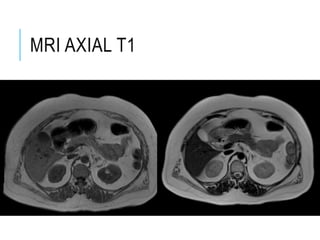

MRI AXIAL T1